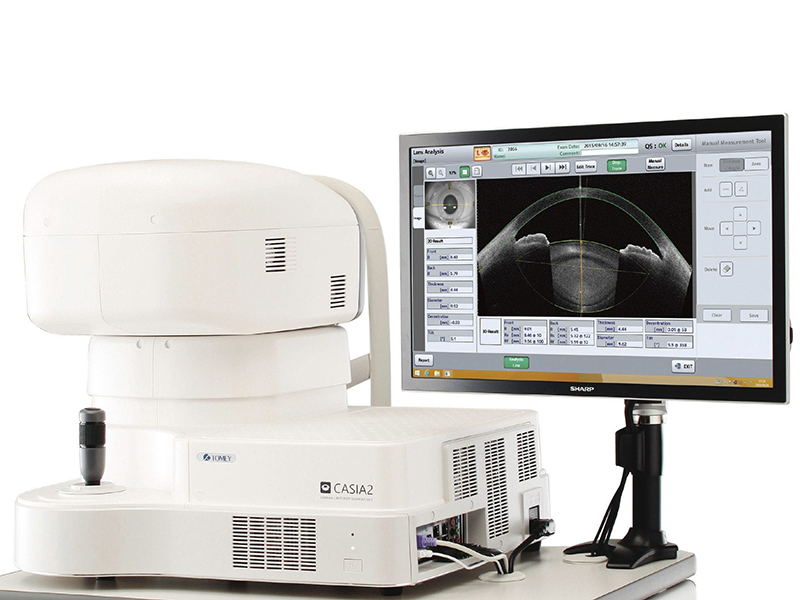

ИЗМЕРИТЕЛЬНЫЙ БЛОК

Разрешение

аксиальная глубина – 10мкм или менее (в тканях), поперечная – 30 мкм или менее (в тканях)

Скорость сканирования

50 000 А-сканов /сек

Диапазон сканирвания

16х16х13 мм

Ход измерительной головы

12х12 мм, 88 мм (ось Х), 40 мм (осьY), 43 мм (ось Z)

Регулировка подставки для подбородка

70 мм

Сенсорный экран

20’’

Габариты (г/ш/в)

530х560х455мм

Вес

33 кг

Режим настройки

ручная, джойстик, сенсорный экран, автонастройка, автоснимки

Тип источника света

смещаемый источник света (SWEPT source)

Длина волны

1 310 нм

Принцип

Домен Фурье

Выходная мощность

Менее 6мВ

ИСТОЧНИК ПИТАНИЯ

Напряжение

100В-240В

Частота

50/60Гц

Потребляемая мощность

170ВА

ОС

Windows 8.1 64 бит

Процессор

Intel Core i7 или выше

Память

8 Гб

SSD или HDD

SSD 128 ГБ и внешняя 2-8 ТБ

Экспорт данных

Принтер (LAN/USB)

Импорт данных

LAN/USB